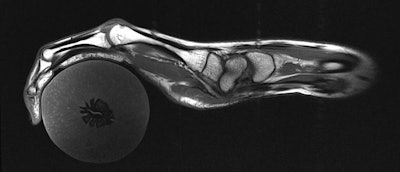

Early results show that the uniquely designed MRI scanner clearly visualizes bones, tendons, ligaments, and their movements. Given its flexibility and sensitivity, the device could someday help diagnose repetitive strain injuries, such as carpal tunnel syndrome, and inflammation from arthritis, as well as other ailments (Nature Biomed Eng, May 8, 2018).

With no electric current created by the MR signal, the new receiver coils no longer create magnetic fields that interfere with their neighbors, thus removing the need for rigid structures to keep the coils in place. The resulting flexibility of the MRI design is "very cool," Cloos said, with the coils stitched into a cotton glove to generate images as the hand moves freely, performing different tasks.

The glove-shaped scanner creates a 3D image that captures the entire hand and wrist. With additional coils and hardware, the researchers could extend the glove farther up the arm.